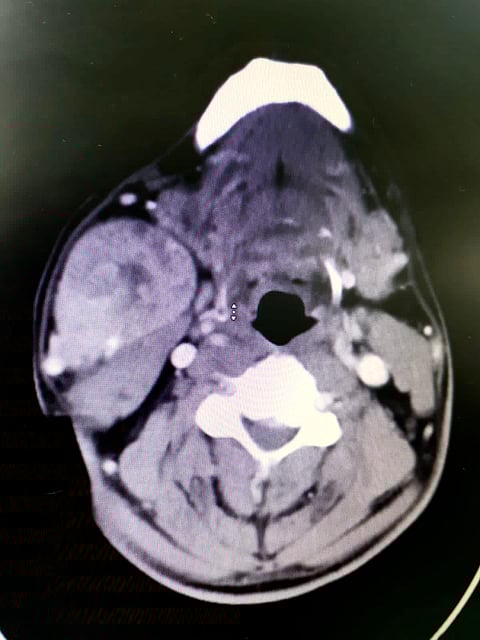

وأوضحت أنه تم إجراء العملية بعد عمل الفحوصات والأشعة المقطعية بالصبغة، وعمل تحاليل شاملة للدم؛ وبناء عليه قرر الفريق الطبي إجراء عملية جراحية، استمرت أكثر من ساعتين.